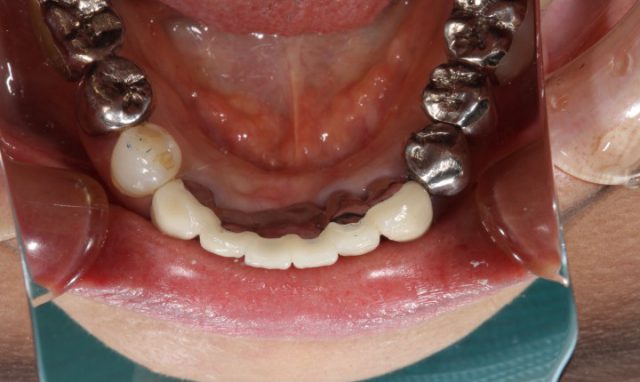

下がってきた歯茎にあわせるように新しい被せ物をつけていくので、術前に比べるととても自然です。今回の患者さまのように欠損している歯をブリッジにより回復する場合にはメタルボンドのような土台を金属でつなげたほうが強度が出ます。

上の歯を治療して以来、逆に下の歯がとても目立ってしまっていたと気になされていた患者さまですが、術後の仕上がりをみてとても喜んでおられました。